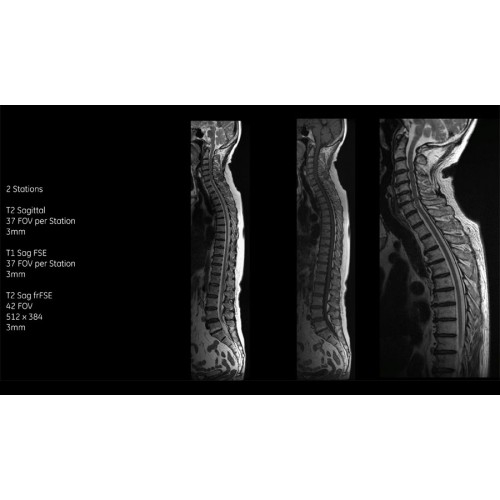

МРТ аппарат GE SIGNA Voyager 1.5T позволяет проводить полный спектр магнитно-резонансных исследований, включая нейровизуализацию, исследования опорно-двигательного аппарата, органов брюшной полости и малого таза, а также специализированные кардиологические программы.